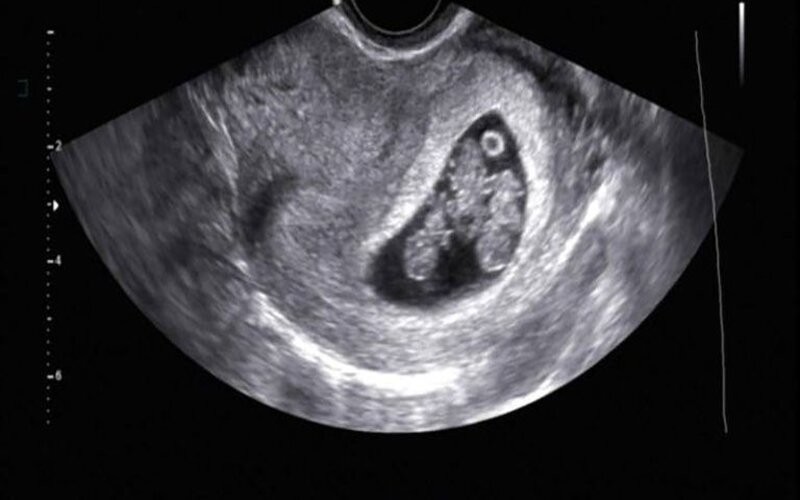

“Me tapé la cara y me puse a llorar. Casi me muero: fui por uno solo y al final eran tres”, recuerda la mamá, del día que se hizo la eco. Mientras intentaba tranquilizarla, María Inés Visco, obstetra y especialista en diagnóstico prenatal, le preguntó si había ido acompañada y salió a buscar a Leonel, que había decidió esperar afuera “para no invadir”, ya que no se trataba de una ecografía tradicional, sino de una trasvaginal.

María Inés Visco, comentó que el caso de Vanina es excepcional. “Se trata de un embarazo monocorial triamniótico, lo que significa que las tres niñas son genéticamente idénticas. Por lo general, uno aprende estas cosas en la universidad, pero después es muy difícil encontrarlas en la vida real. Más, cuando se dan de manera natural como en esta pareja”.

Este tipo de embarazos múltiples se producen cuando un espermatozoide fecunda un óvulo y queda dividido en tres en la primera etapa de gestación. “Como resultado, los bebés comparten la placenta y todas las características físicas, entre ellas, el sexo y el grupo sanguíneo”, explica la ecografista sin disimular su entusiasmo. Y sigue: “Hay que estar dormido para no enamorarse de esto que está pasando. Toda la comunidad médica del Instituto de Diagnóstico Ecográfico (IDE) está muy emocionada”.

En tanto, María Inés Visco aseguró: “Yo sigo maravillada. Las nenas tienen exactamente la misma porción de placenta cada una. A medida que van creciendo, se ve cómo interactúan: cuando le querés enfocar la cara a una, la otra se le tapa con un pie. Es muy divertido”.